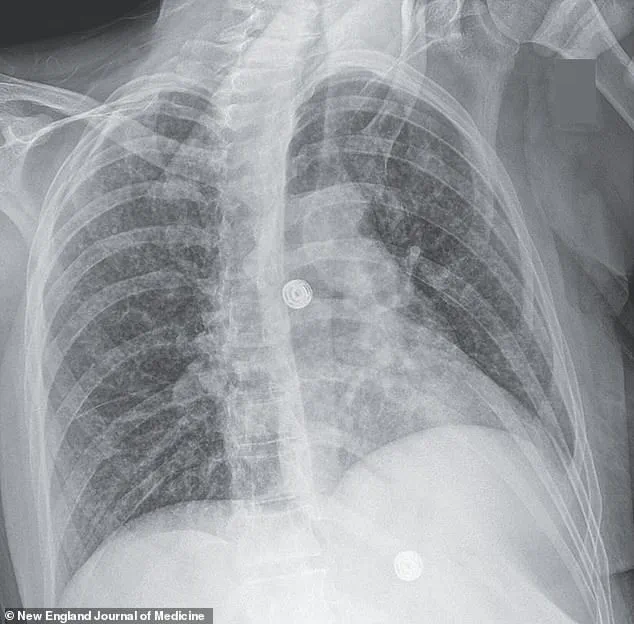

X-ray scans of the woman’s lungs revealed small nodules, a red flag for bacterial infection.

Further imaging and biopsies uncovered lesions in her liver, lymph nodes, pancreas, and brain—indications that the infection had spread far beyond the lungs.

Medical scans revealed nodules in her lungs, an enlarged lymph node, and lesions in her liver, pancreas, and brain—evidence of a TB infection that had spread far beyond its usual confines.